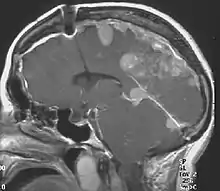

Neurofibromatosis type II (also known as MISME syndrome – multiple inherited schwannomas, meningiomas, and ependymomas) is a genetic condition that may be inherited or may arise spontaneously, and causes benign tumors of the brain, spinal cord, and peripheral nerves. The types of tumors frequently associated with NF2 include vestibular schwannomas, meningiomas, and ependymomas. The main manifestation of the condition is the development of bilateral benign brain tumors in the nerve sheath of the cranial nerve VIII, which is the "auditory-vestibular nerve" that transmits sensory information from the inner ear to the brain. Besides, other benign brain and spinal tumors occur. Symptoms depend on the presence, localisation and growth of the tumor(s), in which multiple cranial nerves can be involved.[2] Many people with this condition also experience vision problems. Neurofibromatosis type II (NF2 or NF II) is caused by mutations of the "Merlin" gene,[3] which seems to influence the form and movement of cells. The principal treatments consist of neurosurgical removal of the tumors and surgical treatment of the eye lesions. Historically the underlying disorder has not had any therapy due to the cell function caused by the genetic mutation.

NF2 is a genetically transmitted condition. Diagnosis is most common in early adulthood (20–30 years); however, it can be diagnosed earlier. NF2 can be diagnosed due to the presence of a bilateral vestibular schwannoma, or an acoustic neuroma, which causes a hearing loss that may begin unilaterally.[15] If a patient does not meet this criterion of diagnosis, they must have a family history of NF2, and present with a unilateral vestibular schwannoma and other associated tumors (cranial meningioma, cranial nerve schwannoma, spinal meningioma, spinal ependymomas, peripheral nerve tumor, spinal schwannoma, subcutaneous tumor, skin plaque). This being said, more than half of all patients diagnosed with NF2 do not have a family history of the condition.[15] Although it has yet to be included into clinical classification, peripheral neuropathy, or damage to the peripheral nerves, which often causes weakness, numbness and pain in the hands and feet, may also lead to a diagnosis of NF2. In children, NF2 can present with similar symptoms, but generally causes "visual disturbances (cataracts, hamartomas), skin tumors, mononeuropathhy (facial paresis, drop foot), symptomatic spinal cord tumors, or non-vestibular intracranial tumors".[15]

Meningiomas and schwannomas occur in around half of patients with NF2. Meningiomas are tumors that are both intracranial and intraspinal. Schwannomas are tumors that are often centered on the internal auditory canal. Patients with NF2 who have meningiomas have a higher risk of mortality, and the treatment can be very challenging. Individuals who develop schwannomas frequently develop hearing loss and deafness.[26] These individuals may also develop tinnitus after being presented with unilateral hearing loss. The first symptom that individuals may encounter is dizziness or imbalance.